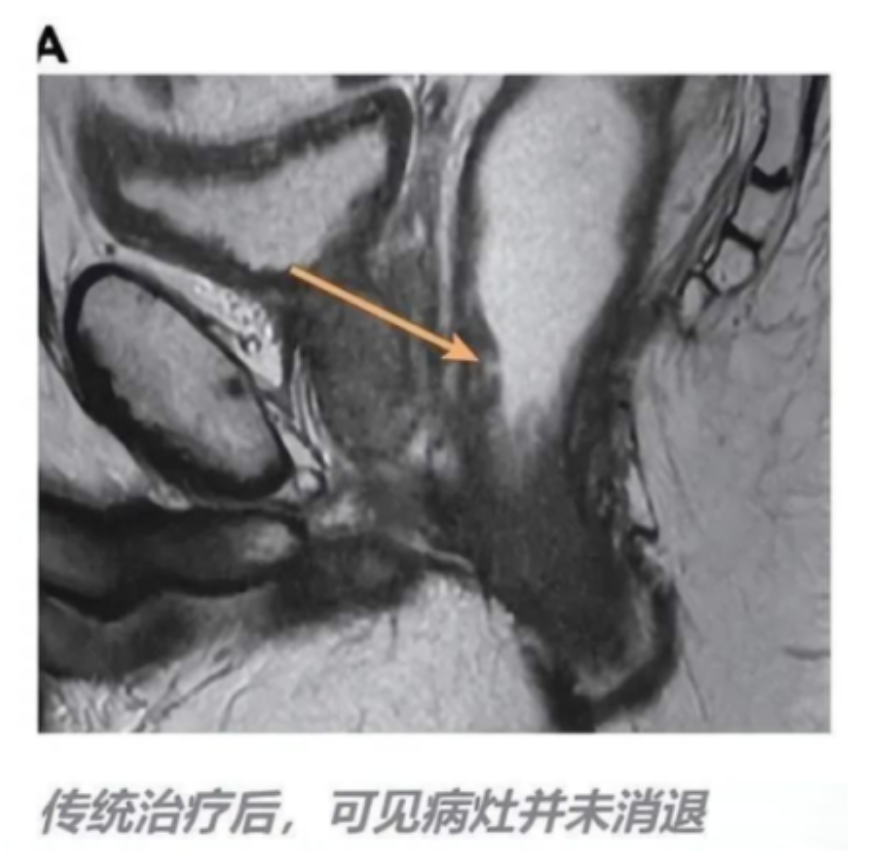

因手术切除边界难定,小徐踏上了 FOLFOX 化疗与放化疗并行之路,每日口服 1650mg 卡培他滨。但六周后的核磁共振结果如同一记重锤,病灶毫无退缩迹象。

图片